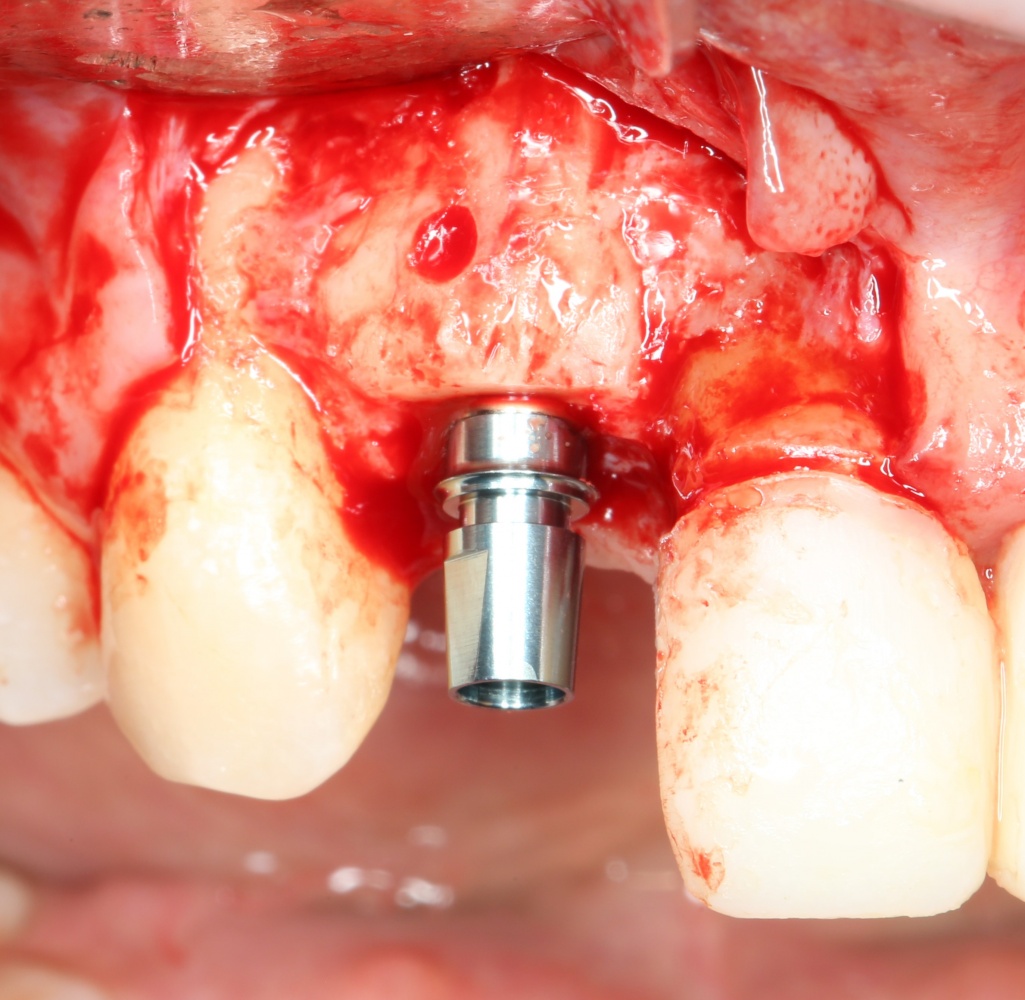

Кстати, обрати внимание на ширину альвеолярного гребня (левая картинка). Она чуть меньше 3 мм. Это объясняет, почему я засомневался в возможности установки имплантатов одновременно с остеопластикой. Понятно и без КЛКТ.

Возвращаемся к основной операционной области. Еще раз посмотрим на альвеолярный гребень, поофигеваем от его ширины и моих грандиозных планов:

Я зафиксировал костный блок практически без адаптации на несколько винтов. Обрати внимание, что винты находятся в зоне, где не планируется установка имплантатов. Фиксация должна быть надежной, поскольку мне еще предстояла подготовка лунок для имплантатов. Трех винтов для этого вполне достаточно.

Напомню, что для этой работы я выбрал субкрестальные имплантаты Ankylos C/X. Они прекрасно сочетаются с любым методом остеопластики.

Глянем на то, что получилось: